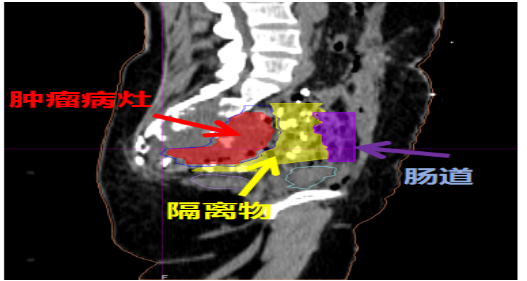

“外科+重离子”新策略:对于肿瘤与直肠、肠道界限不清(如骶尾部肿瘤)的患者,武威中心现在采用首创的SPACER技术——通过手术暂时将直肠与肿瘤用纱垫隔开,再进行重离子照射。SPACER技术解决了因紧邻肠管而无法给足根治剂量的问题。

手术将肿瘤与肠管间置入纱扩垫,隔开肠管,保护肠管

置入隔离物大纱垫

重(碳)离子治疗靶区勾画,瘤体与危及器官间手术置入隔离组织物,为目标肿瘤与周围正常组织提供了足够的距离,从而可以给肿瘤以充足的根治剂量。

手术将肿瘤与肠管间置入纱扩垫,隔开肠管,保护肠管,当天完成重离子灭活肿瘤

靶区勾画:GTV-红色 结肠-紫色 隔离组织物-黄色